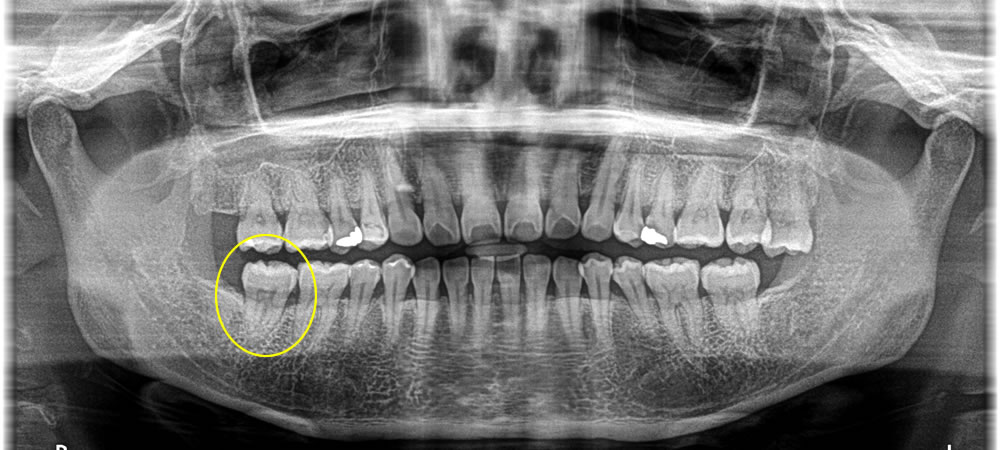

右上奥歯の欠損部分をインプラントで治療した症例

年齢

60代

性別

男性